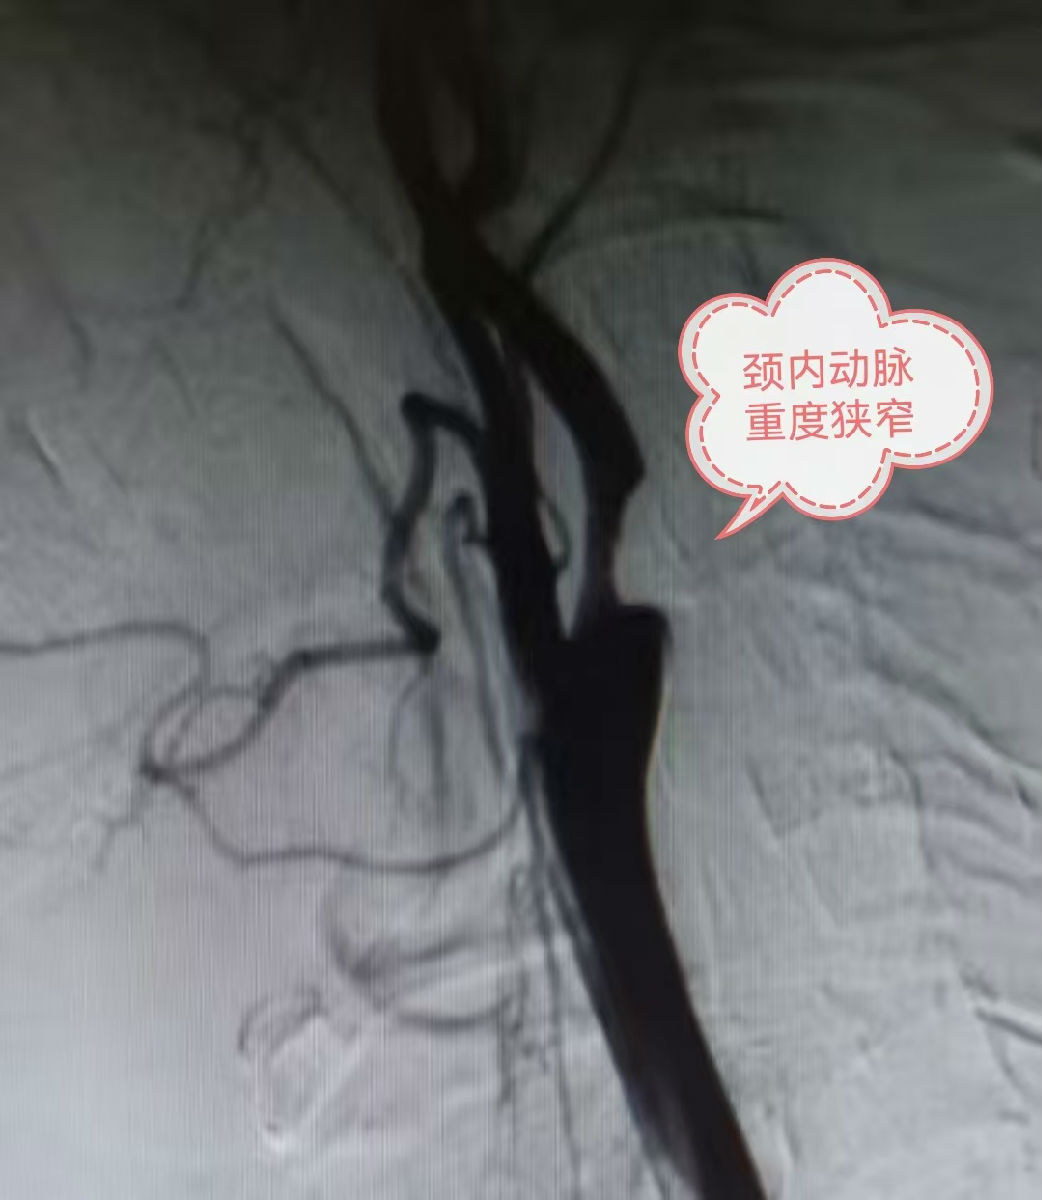

54岁的王师傅因“反复发作性头晕1年”,在家人的陪同下来到西安医学院附属宝鸡医院神经外科就诊。经颈动脉超声及全脑血管造影(DSA)检查,明确诊断为“左侧颈内动脉起始部重度狭窄(狭窄程度>70%)” 。这意味着为大脑输送血液的“生命线”已近乎堵塞,患者随时面临大面积脑梗死的致命风险。

术后即刻血管造影显示:原重度狭窄处管腔恢复通畅,大脑供血显著改善。患者麻醉苏醒后四肢活动自如、语言清晰,无任何神经功能缺损表现。目前,患者已康复出院。